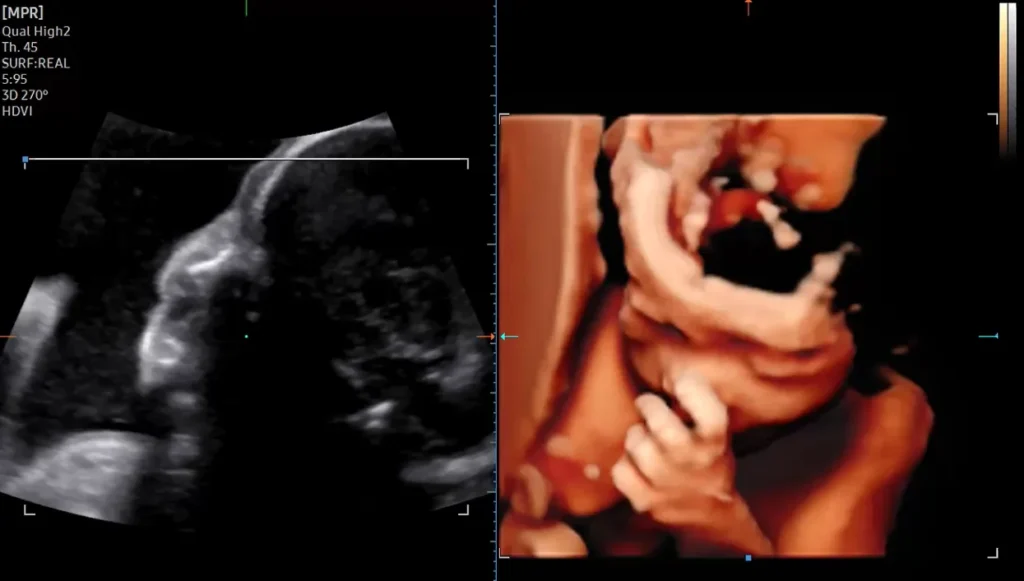

3D/4D Fetal / Obstetric Ultrasound

High-definition 3D Fetal images for better anatomical assessment and parental bonding.